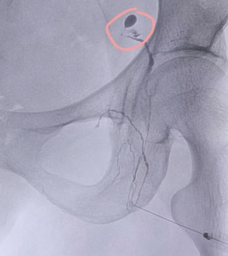

李女士于外院行宫颈手术后每日盆腔引流液约600ml,持续1月余,辗转于西安多个医院,治疗效果欠佳。后入住东院肿瘤外科。行盆腔淋巴管显影,术中明确定位淋巴漏位置,并行淋巴管栓塞。术后很快引流液量降低至正常范围。